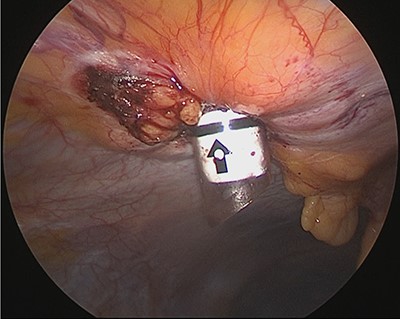

Under general anesthesia, with the patient in the lithotomy position, a 5-mm trocar was inserted into the lower right abdomen using the optical method. Observation of the abdominal cavity revealed a hernia orifice with a diameter of ~1 cm at the upper aspect of the umbilicus (Fig. 3). Two additional 5-mm trocars were inserted into the left side of the abdomen. The hernia sac was significant scarring. We then made an incision around the hernia orifice using a hook-type electrocautery electrode to expose the muscle layer (Fig. 4). The hernia sac was pushed from the surface of the body using a pean, inverted into the abdominal cavity, and excised as much as possible using electrocautery (Fig. 5). At that point, we employed the VersaOne™ Fascial Closure System to close the fascia and peritoneum at the port site.